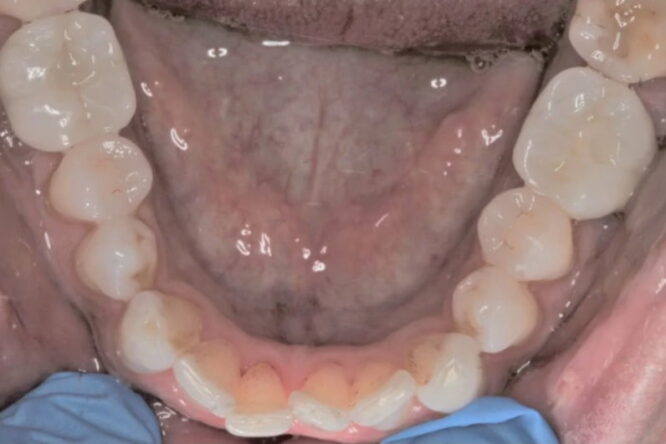

This patient lost his two of his lower molar teeth. Implants were placed on either side to replace the lost teeth as they were a long term option and did not damage any of his other teeth.